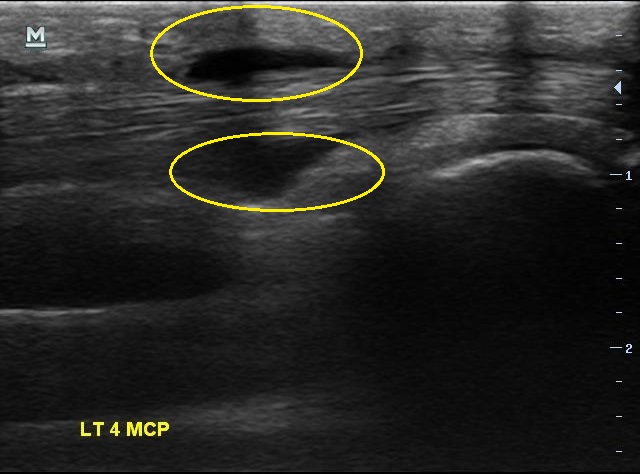

X-ray 검사상에는 특별한건 보이지 않습니다. 초음파 검사에서는.... 4번째 손가락을 굽혀주는 힘줄(4th flexor digitorum tendon)에 염증이 생겨있습니다.

2주 전보다 힘줄에 염증이 훨씬 심해져 있었습니다. 그리고

이번에는 한 부위만이 아니라 손가락 굽힘 힘줄을 따라 전체적으로 염증이 퍼져있습니다.